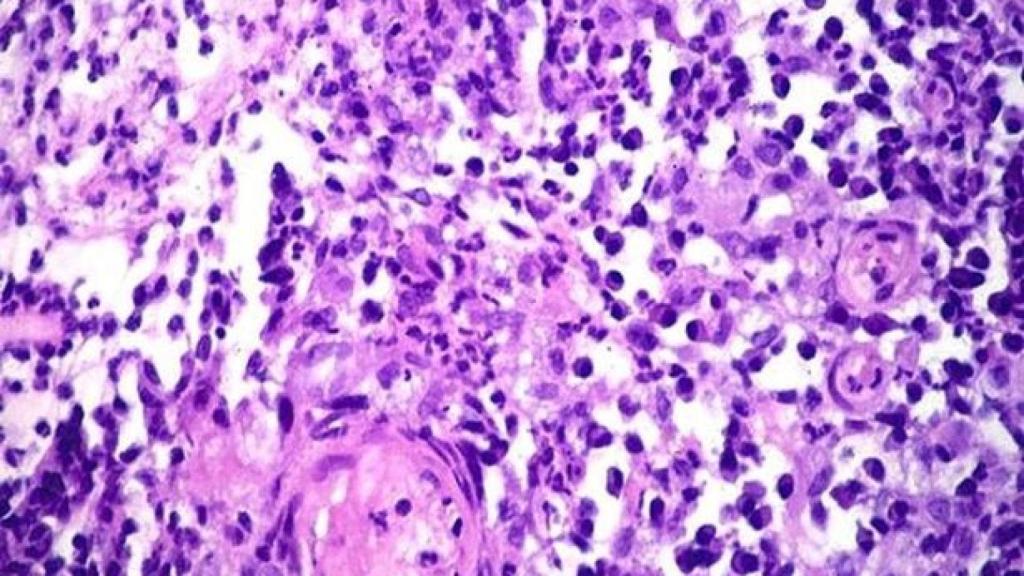

La donovanosis es popularmente conocida como "enfermedad come-carne". La causa de la ETS es el microorganismo Klebsiella granulomatis. No es nada común en el continente europeo, y en Estados Unidos no suelen verse más de 100 casos al año, según los Institutos Nacionales de Salud del país norteamericano.

La donovanosis o granuloma inguinal es capaz de destruir el tejido genital. Se trata de una enfermedad común en áreas tropicales y subtropicales -sudeste de la India, Guyana, el Caribe, Centro de Australia, sur de África y Nueva Guinea-, pero existen unos pocos casos que logran llegar a países occidentales. La mayoría de estos casos los transmiten viajeros que han estado en los países de origen de la enfermedad, o habitantes de estos mismos países que han decidido viajar fuera de las zonas endémicas.

Los hombres suelen ser los más afectados, representando el doble de casos de contagio que las mujeres, aunque en ambos géneros la infección suele producirse entre los 20 y los 40 años. Los síntomas pueden iniciarse de forma precoz, la primera semana tras el contagio, o incluso tras doce semanas a partir del mismo. En el 50% de los casos se producen úlceras en la zona anal, pudiendo aparecer protuberancias rojas y pequeñas en la zona genital o perianal. Posteriormente, se produce una descamación de la piel y estas neoformaciones se convierten en nódulos o granulomas, no dolorosos, pero los cuales sangran con mucha facilidad con el mínimo roce.

Poco a poco la enfermedad va diseminándose lentamente y acaba por destruir el tejido genital, pudiendo afectar a la ingle y el tejido periférico. De forma resumida, como ya anuncia el medio Liverpool Echo, la enfermedad "desintegra la piel y la carne" del paciente afecto. En las últimas etapas de la misma, estas lesiones pueden llegar a imitar a un cáncer genital avanzado.